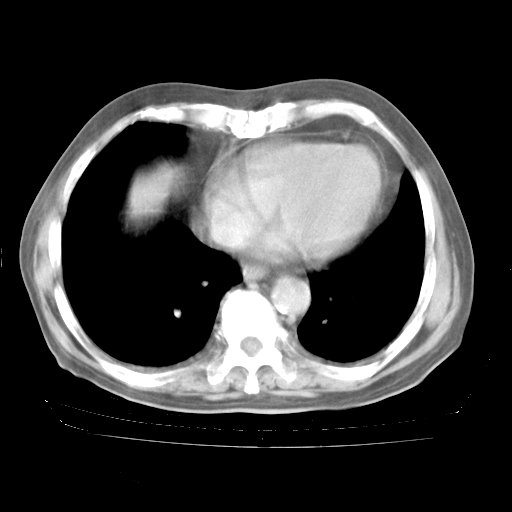

4月28日肺部CT——再次出现类似去年5月9日——透光度降低,“间质性”改变。